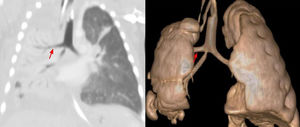

A 41-day-old boy with history of corrected esophageal atresia (EA) with distal fistula at 4th day of life and tracheomalacia, presented a second episode of pneumonia. Computerized tomography (CT) (Fig. 1) followed by virtual bronchoscopy, revealed consolidation in the right lung and an anomaly of the bronchial segmentation, with the right upper lobe's bronchus originating directly from the trachea. The patient was discharged from the hospital following medical treatment. Afterwards, he had two more episodes of pneumonia, however, now he has remained clinically stable for almost two years.

Tracheal trifurcation is an uncommon condition, with an incidence up to 2%.1 Patients can be asymptomatic or present recurrent right-sided pneumonia or atelectasis. Expectant management is preferred, however, in recurrence of symptoms, surgical excision of the involved segment may be necessary.2

Tracheal bronchus (TB) may be associated with EA and significant risks during tracheal intubation.

Flexible bronchoscopy provides a clear view of the anomaly and CT or virtual bronchoscopy allows noninvasive diagnosis. Therefore, flexible bronchoscopy or CT during childhood is proposed for all patients with EA, in order to rule out associated tracheomalacia and TB, and the presence of TB should be considered in child being evaluated for recurrent right-sided pneumonia.